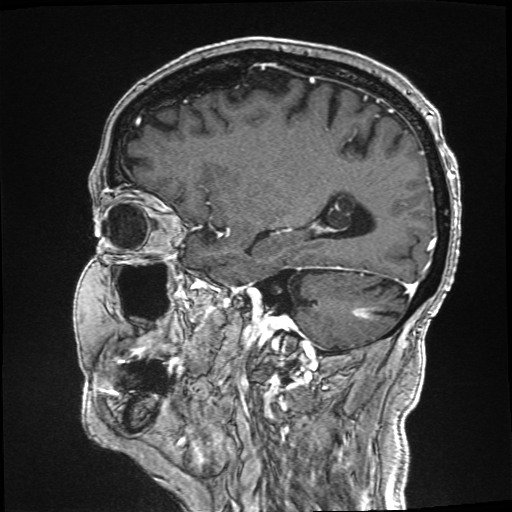

4.3 Evaluation on real low-dose images

Refer to captionRefer to caption𝐱PCsubscript𝐱PC\mathbf{x}_{\mathrm{PC}}bold_x start_POSTSUBSCRIPT roman_PC end_POSTSUBSCRIPTRefer to captionRefer to caption𝐱LDsubscript𝐱LD\mathbf{x}_{\mathrm{LD}}bold_x start_POSTSUBSCRIPT roman_LD end_POSTSUBSCRIPTRefer to captionRefer to caption𝐱SDsubscript𝐱SD\mathbf{x}_{\mathrm{SD}}bold_x start_POSTSUBSCRIPT roman_SD end_POSTSUBSCRIPTRefer to captionRefer to captionAm-3D [14]Refer to captionRefer to captionPa-2.5D [8]Refer to captionRefer to caption𝐱~SDsubscript~𝐱SD\tilde{\mathbf{x}}_{\mathrm{SD}}over~ start_ARG bold_x end_ARG start_POSTSUBSCRIPT roman_SD end_POSTSUBSCRIPT (ours)ptPhilips Achieva 3TGadobutrol dLD=0.10subscript𝑑LD0.10d_{\mathrm{LD}}=0.10italic_d start_POSTSUBSCRIPT roman_LD end_POSTSUBSCRIPT = 0.10ptPhilips Ingenia 1.5TGadoterate dLD=0.33subscript𝑑LD0.33d_{\mathrm{LD}}=0.33italic_d start_POSTSUBSCRIPT roman_LD end_POSTSUBSCRIPT = 0.33Refer to captionRefer to caption𝐱PCsubscript𝐱PC\mathbf{x}_{\mathrm{PC}}bold_x start_POSTSUBSCRIPT roman_PC end_POSTSUBSCRIPTRefer to captionRefer to caption𝐱LDsubscript𝐱LD\mathbf{x}_{\mathrm{LD}}bold_x start_POSTSUBSCRIPT roman_LD end_POSTSUBSCRIPTRefer to captionRefer to caption𝐱SDsubscript𝐱SD\mathbf{x}_{\mathrm{SD}}bold_x start_POSTSUBSCRIPT roman_SD end_POSTSUBSCRIPTRefer to captionRefer to captionAm-3D [14]Refer to captionRefer to captionPa-2.5D [8]Refer to captionRefer to caption𝐱~SDsubscript~𝐱SD\tilde{\mathbf{x}}_{\mathrm{SD}}over~ start_ARG bold_x end_ARG start_POSTSUBSCRIPT roman_SD end_POSTSUBSCRIPT (ours)ptPhilips Achieva 3TGadobutrol dLD=0.10subscript𝑑LD0.10d_{\mathrm{LD}}=0.10italic_d start_POSTSUBSCRIPT roman_LD end_POSTSUBSCRIPT = 0.10ptPhilips Ingenia 1.5TGadoterate dLD=0.33subscript𝑑LD0.33d_{\mathrm{LD}}=0.33italic_d start_POSTSUBSCRIPT roman_LD end_POSTSUBSCRIPT = 0.33Refer to captionRefer to caption𝐱PCsubscript𝐱PC\mathbf{x}_{\mathrm{PC}}bold_x start_POSTSUBSCRIPT roman_PC end_POSTSUBSCRIPTRefer to captionRefer to caption𝐱LDsubscript𝐱LD\mathbf{x}_{\mathrm{LD}}bold_x start_POSTSUBSCRIPT roman_LD end_POSTSUBSCRIPTRefer to captionRefer to caption𝐱SDsubscript𝐱SD\mathbf{x}_{\mathrm{SD}}bold_x start_POSTSUBSCRIPT roman_SD end_POSTSUBSCRIPTRefer to captionRefer to captionAm-3D [14]Refer to captionRefer to captionPa-2.5D [8]Refer to captionRefer to caption𝐱~SDsubscript~𝐱SD\tilde{\mathbf{x}}_{\mathrm{SD}}over~ start_ARG bold_x end_ARG start_POSTSUBSCRIPT roman_SD end_POSTSUBSCRIPT (ours)ptPhilips Achieva 3TGadobutrol dLD=0.10subscript𝑑LD0.10d_{\mathrm{LD}}=0.10italic_d start_POSTSUBSCRIPT roman_LD end_POSTSUBSCRIPT = 0.10ptPhilips Ingenia 1.5TGadoterate dLD=0.33subscript𝑑LD0.33d_{\mathrm{LD}}=0.33italic_d start_POSTSUBSCRIPT roman_LD end_POSTSUBSCRIPT = 0.33Refer to captionRefer to caption𝐱PCsubscript𝐱PC\mathbf{x}_{\mathrm{PC}}bold_x start_POSTSUBSCRIPT roman_PC end_POSTSUBSCRIPTRefer to captionRefer to caption𝐱LDsubscript𝐱LD\mathbf{x}_{\mathrm{LD}}bold_x start_POSTSUBSCRIPT roman_LD end_POSTSUBSCRIPTRefer to captionRefer to caption𝐱SDsubscript𝐱SD\mathbf{x}_{\mathrm{SD}}bold_x start_POSTSUBSCRIPT roman_SD end_POSTSUBSCRIPTRefer to captionRefer to captionAm-3D [14]Refer to captionRefer to captionPa-2.5D [8]Refer to captionRefer to caption𝐱~SDsubscript~𝐱SD\tilde{\mathbf{x}}_{\mathrm{SD}}over~ start_ARG bold_x end_ARG start_POSTSUBSCRIPT roman_SD end_POSTSUBSCRIPT (ours)ptPhilips Achieva 3TGadobutrol dLD=0.10subscript𝑑LD0.10d_{\mathrm{LD}}=0.10italic_d start_POSTSUBSCRIPT roman_LD end_POSTSUBSCRIPT = 0.10ptPhilips Ingenia 1.5TGadoterate dLD=0.33subscript𝑑LD0.33d_{\mathrm{LD}}=0.33italic_d start_POSTSUBSCRIPT roman_LD end_POSTSUBSCRIPT = 0.33Refer to captionRefer to caption𝐱PCsubscript𝐱PC\mathbf{x}_{\mathrm{PC}}bold_x start_POSTSUBSCRIPT roman_PC end_POSTSUBSCRIPTRefer to captionRefer to caption𝐱LDsubscript𝐱LD\mathbf{x}_{\mathrm{LD}}bold_x start_POSTSUBSCRIPT roman_LD end_POSTSUBSCRIPTRefer to captionRefer to caption𝐱SDsubscript𝐱SD\mathbf{x}_{\mathrm{SD}}bold_x start_POSTSUBSCRIPT roman_SD end_POSTSUBSCRIPTRefer to captionRefer to captionAm-3D [14]Refer to captionRefer to captionPa-2.5D [8]Refer to captionRefer to caption𝐱~SDsubscript~𝐱SD\tilde{\mathbf{x}}_{\mathrm{SD}}over~ start_ARG bold_x end_ARG start_POSTSUBSCRIPT roman_SD end_POSTSUBSCRIPT (ours)ptPhilips Achieva 3TGadobutrol dLD=0.10subscript𝑑LD0.10d_{\mathrm{LD}}=0.10italic_d start_POSTSUBSCRIPT roman_LD end_POSTSUBSCRIPT = 0.10ptPhilips Ingenia 1.5TGadoterate dLD=0.33subscript𝑑LD0.33d_{\mathrm{LD}}=0.33italic_d start_POSTSUBSCRIPT roman_LD end_POSTSUBSCRIPT = 0.33Refer to captionRefer to caption𝐱PCsubscript𝐱PC\mathbf{x}_{\mathrm{PC}}bold_x start_POSTSUBSCRIPT roman_PC end_POSTSUBSCRIPTRefer to captionRefer to caption𝐱LDsubscript𝐱LD\mathbf{x}_{\mathrm{LD}}bold_x start_POSTSUBSCRIPT roman_LD end_POSTSUBSCRIPTRefer to captionRefer to caption𝐱SDsubscript𝐱SD\mathbf{x}_{\mathrm{SD}}bold_x start_POSTSUBSCRIPT roman_SD end_POSTSUBSCRIPTRefer to captionRefer to captionAm-3D [14]Refer to captionRefer to captionPa-2.5D [8]Refer to captionRefer to caption𝐱~SDsubscript~𝐱SD\tilde{\mathbf{x}}_{\mathrm{SD}}over~ start_ARG bold_x end_ARG start_POSTSUBSCRIPT roman_SD end_POSTSUBSCRIPT (ours)ptPhilips Achieva 3TGadobutrol dLD=0.10subscript𝑑LD0.10d_{\mathrm{LD}}=0.10italic_d start_POSTSUBSCRIPT roman_LD end_POSTSUBSCRIPT = 0.10ptPhilips Ingenia 1.5TGadoterate dLD=0.33subscript𝑑LD0.33d_{\mathrm{LD}}=0.33italic_d start_POSTSUBSCRIPT roman_LD end_POSTSUBSCRIPT = 0.33Refer to captionRefer to caption𝐱PCsubscript𝐱PC\mathbf{x}_{\mathrm{PC}}bold_x start_POSTSUBSCRIPT roman_PC end_POSTSUBSCRIPTRefer to captionRefer to caption𝐱LDsubscript𝐱LD\mathbf{x}_{\mathrm{LD}}bold_x start_POSTSUBSCRIPT roman_LD end_POSTSUBSCRIPTRefer to captionRefer to caption𝐱SDsubscript𝐱SD\mathbf{x}_{\mathrm{SD}}bold_x start_POSTSUBSCRIPT roman_SD end_POSTSUBSCRIPTRefer to captionRefer to captionAm-3D [14]Refer to captionRefer to captionPa-2.5D [8]Refer to captionRefer to caption𝐱~SDsubscript~𝐱SD\tilde{\mathbf{x}}_{\mathrm{SD}}over~ start_ARG bold_x end_ARG start_POSTSUBSCRIPT roman_SD end_POSTSUBSCRIPT (ours)ptPhilips Achieva 3TGadobutrol dLD=0.10subscript𝑑LD0.10d_{\mathrm{LD}}=0.10italic_d start_POSTSUBSCRIPT roman_LD end_POSTSUBSCRIPT = 0.10ptPhilips Ingenia 1.5TGadoterate dLD=0.33subscript𝑑LD0.33d_{\mathrm{LD}}=0.33italic_d start_POSTSUBSCRIPT roman_LD end_POSTSUBSCRIPT = 0.33

Figure 6: Qualitative evaluation on the RLS dataset. The top row depicts a 33%percent3333\%33 % low-dose sample, where the yellow zoom highlights the lesion. The bottom row shows a case with a 10%percent1010\%10 % real low-dose image and the lesion is marked by the yellow circles.

Next, Am-3D, Pa-2.5D, and our approach trained on the RLD dataset are evaluated on the 77777777 RLD test images. Here, ADC images are additionally fed into Am-3D as required [14].

A qualitative comparison of RLD test samples is shown in Figure 6. The required skull stripping and non-linear intensity normalization of Am-3D are readily apparent. Thus, a quantitative comparison to the target 𝐱SDsubscript𝐱SD\mathbf{x}_{\mathrm{SD}}bold_x start_POSTSUBSCRIPT roman_SD end_POSTSUBSCRIPT is not reasonable. Nevertheless, the CE signal strength in pathological regions (highlighted by the yellow circles) is well visible despite too smooth output images. The internal morphology and the border delineation also exhibit blurring. Pa-2.5D yields better image quality but the contrast strength in pathological regions is not well captured. In particular, the contrast signal overshoots for the 33%percent3333\%33 % low-dose scan in the first row and undershoots for the 10%percent1010\%10 % scan at the bottom, although the training dataset contains low-dose images at both dose levels. Our approach yields the highest image quality and predicts the contrast enhancement more accurately due to the focus on the enhancement signal and the conditional embeddings. As a result, our approach generates CE images preserving the image quality of the inputs by avoiding the synthesis of anatomical or noise patterns.